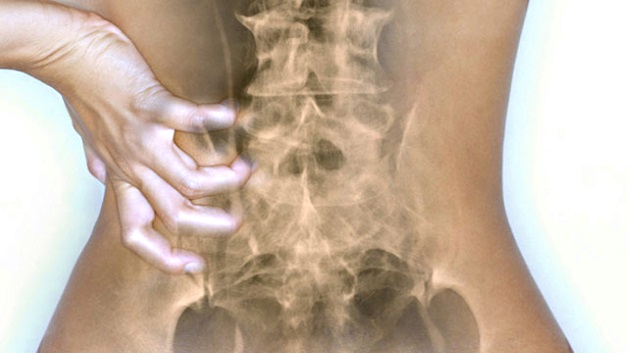

С точки зрения психосоматики проблемы с позвоночником обусловлены дисбалансом физического и психического состояния. Остеохондроз указывает на то, что требуется неотложная помощь. Эти сигналы исходят от самого организма, который страдает от ежедневных забот, стресса, физических нагрузок – это главные причины боли и усталости спины.

Дегенеративные изменения в межпозвонковых дисках вызваны мышечным напряжением, которое приводит к неравномерной нагрузке на позвоночник. В результате ткани деформируются, нарушается кровообращение и метаболизм. Впоследствии появляется слабость, недомогание, онемение лица и конечностей, скованность движений. Патологический процесс в каждом отделе позвоночника развивается под влиянием определенных болезненных эмоций:

- Остеохондроз шейного отдела вызван спазмами мышц лица, затылка и шеи. Это происходит чаще всего, когда человек подавляет негативные эмоции, такие как страх, ярость, печаль. С точки зрения психосоматики проблема также связана с отсутствием внутренней гибкости и упрямством, а также ощущением собственной ненужности и отсутствия привязанности со стороны окружающих.

- Остеохондроз грудного отдела позвоночника вызывает мышечный зажим в области верхней половины тела. Боли на участке между шеей и талией появляются из-за ощущения неуверенности в себе, отсутствия моральной поддержки. Л. Хей и Л. Бурбо сходятся в том, что дистрофические нарушения в этой части спины происходят и потому, что человек пытается сдержать чувство любви.

- Остеохондроз поясничного отдела развивается из-за продолжительных мышечных спазмов в нижней части спины, ягодицах и ногах. Скорей всего, человек испытывает чувство вины и «застрял» в прошлом. Проблемы с поясницей знакомы и тем, кто страшится потерять материальное благополучие, а также тем, кто уже испытывает финансовые трудности.